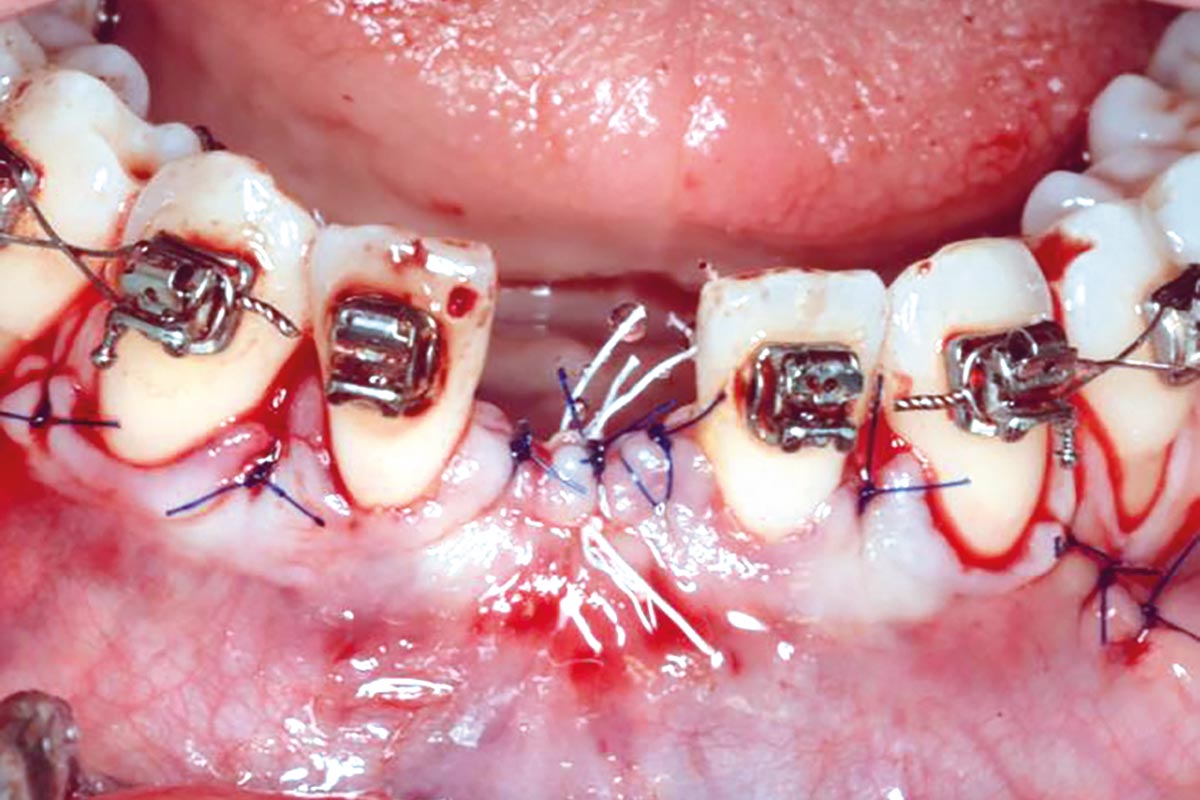

Regenerative corticotomy to compensate lower incisor malocclusion with cerabone® and mucoderm®

Initial view of the clinical case: Class III malocclusion

Treatment plan: Regenerative corticotomy (PAOO)